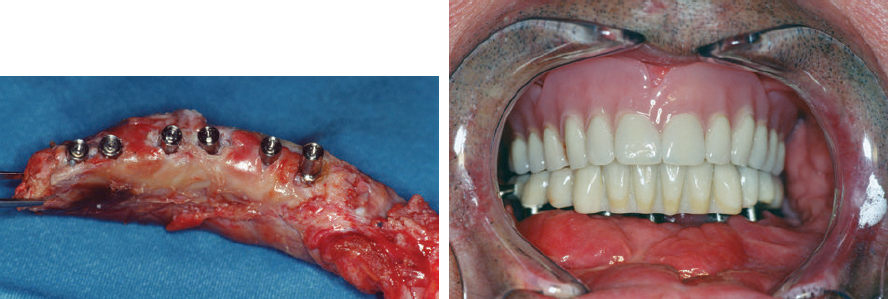

CHAPTER Modern plastic surgery concepts are based on the paradigm that plastic surgery must restore function as well as anatomy in all cases, regardless of the indication for surgery. In the case of facial plastic surgery, respecting the facial proportions is an elementary prerequisite for achieving an aesthetic reconstruction.1 The facial skeleton is a lightweight, mechanically stable structure that contains pneumatized cavities, houses organ systems, and allows for the fixation of the facial soft tissue envelope in a way that maintains musculoskeletal balance. In the case of loss or aplasia of facial parts, facial disfigurement increases in parallel with the extent of the maxillofacial defect. In this situation, ignoring the functional anatomy during the reconstruction effort invariably results in unsatisfactory outcomes. Since the introduction of microsurgical flap transfer, other methods of regenerative plastic surgery involving the induction of bone and soft tissues in surgical protocols with advanced block-grafting techniques, including prefabricated composite grafts and distraction osteogenesis and histogenesis, have been introduced and can help avoid unfavorable results in patients with severe maxillofacial defects. The bone–muscle crosstalk, which is associated with the regenerative plastic surgery methods mentioned earlier, has beneficial clinical effects on the musculoskeletal balance of the face and is useful for achieving a full rehabilitation. Restorative plastic surgery requires the simultaneous reconstruction of maxillofacial aesthetics and function in all cases, regardless of the indication for surgery, and relies on the surgical concept of like-with-like reconstruction combined with the skeletal rearrangement of the disfigured face. By considering aesthetics and function as an inseparable unit during the induction of functional tissues, the historical separation between plastic reconstructive and aesthetic surgery has been broken. Summary Box Complications in Maxillofacial Reconstruction • Absence of physiologic mucosal lining and gingiva • Facial deformity • Need for repeat bone grafts • Oral mobility loss • Implant loss • Excessive mucous secretion • Persistent peristalsis • Maceration • Hair growth The face is involved in speaking, mastication, deglutition, and effortless breathing, and these functions dictate the main objective of any facial treatment: to restore physiological function. The reconstruction of the face, a pneumatized, lightweight, mechanically stable structure to which the facial soft tissue envelope is fixed to maintain musculoskeletal balance, has proven to be a surgical challenge. Fig. 50.1 (a) An unfavorable result caused by intraoral bulkiness in a 58-year-old woman after hemimaxillectomy and reconstruction with an osseomyocutaneous flap. (b) An unfavorable result caused by extraoral “sinus bulkiness” in a 27-year-old patient with loss of the maxilla after tumor surgery and postoperative radiotherapy. Combination of prefabricated scapular flap and obturation of the sinus with a teres major flap. (c) An unfavorable result caused by “bony bulkiness” in a 57-year-old patient after microsurgical reconstruction of the mandible, tongue, and mouth floor with an iliac prefabricated composite graft and external oblique muscle free flap, first described in 1997. (a From Zimpfer M. Department of Anesthesiology and General Intensive Care University of Vienna 1996–2000 Patient Care–Teaching–Research, self-published; b,c from Holle J, Vinzenz K, Würinger E, Kulenkampff KJ, Saidi M. The prefabricated combined scapula flap for bony and soft-tissue reconstruction in maxillofacial defects—a new method. Plast Reconstr Surg 1996;98(3):542–552.) Among the established core principles of craniofacial surgery including “safe approaches, careful designed osteotomies and rigid skeletal fixation”2; advanced bone grafting techniques using the induction of specialized hard and soft tissues in the reconstruction effort are part of the trendsetting advances in regenerative plastic surgery.2 Vascularized osseous, osseocutaneous and myocutaneous free flaps, preferably taken from the fibula, scapula or iliac crest, are standard techniques in facial plastic surgery today.3 The techniques of soft tissue flaps and the microsurgical revascularization of transplants in the maxillofacial area, on the other hand, have not changed significantly since their introduction and are not discussed further here. From a functional point of view, the shortcomings of the use of the current standard free flap methods in facial plastic surgery are as follows: • Closure in severe defects with myocutaneous flaps, irrespective of dermal texture4 • Obturation of pneumatized cavities6 • Reconstruction of a bony framework rather than restoration of the anatomy7 In addition, the current free flap methods occasionally result in bulkiness, which prevents the satisfactory restoration of aesthetics and function5–7 (Fig. 50.1). Stepwise adaptations and corrections can help to achieve acceptable clinical outcomes, but only in the case of mandibular reconstructions6 (Fig. 50.2). Fig. 50.2 Stepwise aesthetic and functional rehabilitation by trimming bulky flaps and integrating implant restoration. (From Holle J, Vinzenz K, Würinger E, Kulenkampff KJ, Saidi M. The prefabricated combined scapula flap for bony and soft-tissue reconstruction in maxillofacial defects—a new method. Plast Reconstr 1996;98(3):542-552.) For the reconstruction of a pneumatized midface, these free flap techniques are inappropriate, which has led to the trend of patient-specific implants and full-face transplantation.8–10 There is a flowing transition between tissue deficiency and defect, and if these persist long enough, they are usually combined with facial disfigurement; therefore complex surgical protocols, rather than simple free flap techniques, are necessary to avoid unfavorable results. The surgical concept of like-with-like restoration in the case of the oral and maxillofacial anatomy includes both the reconstruction of missing tissues and the rearrangement of the skeletal architecture of the face to achieve acceptable aesthetic and functional results, which can be best illustrated in cleft patients. Two aspects must be taken into account during the treatment of maxillofacial deficiencies or defects: 1. Like-with-like reconstruction based on the three “identities,” namely, identical size, identical shape, and identical tissue structure to those of the recipient site.6,11,12 2. Correction of facial disfigurement using grafts and/or surgical orthognathic procedures.13,14 Depending on the extent of the tissue deficiency, a series of surgical methods have been described for different indications in maxillofacial surgery: • Osteoplastic reconstruction (e.g., “stack plasty”) of the alveolus and osteoplasty of tertiary clefts14 • Prefabrication and prelamination of osseous grafts for the reconstruction of large alveolar defects15 • Complex prefabricated grafts for microsurgical reconstruction of the maxilla and midface6,12,16,17 From the point of view of functional anatomy, there are four problems that need to be overcome: 1. Reconstruction of a pneumatized, lightweight skeletal structure with mechanical stability 2. Establishment of a stable inner lining of cavities 3. Establishment of gingiva that is resistant to masticatory loading 4. Prevention of graft inflammation, especially at the implant site Before the development of prefabricated composite grafts, the inner lining of the oral cavity was reconstructed using full- or split-thickness skin grafts, intestinal grafts, and mucosal grafts.4,18,19 However, hair growth, maceration, persistent peristalsis, and excessive mucous secretion have diminished the acceptability of these grafts for the replacement of the oral lining. Furthermore, a high rate of implant loss was observed with these grafts because of deep and persistently inflamed pockets around the site where the dental implant penetrated the gingiva. Moreover, attempts at reconstruction with mucosal prelamination of fasciocutaneous flaps failed because of severe scarring of the lining combined with further loss of oral mobility, particularly in the case of reconstructions of the floor of the mouth.18 Fig. 50.3 The surgical procedure for prefabricating composite flaps from the scapula (a) and iliac crest (b). PTFE, Polytetrafluoroethylene. Fig. 50.4 Reconstruction of the mandible with a prefabricated iliac composite graft with a periodontal unit consisting of the bony alveolus, gingiva, and implant restoration in a 57-year-old man who had undergone mandibulectomy. (Reproduced from Vinzenz K, Schaudy C. Osteoplastic surgery of the face—state of the art and future aspects. Eur Surg 2011;43(5):270-283, with permission from Springer-Verlag Wien.) Dermal prelamination of the bone, which was first cited in 1996,6,12 is a complex prefabricated composite graft that allows the restoration of the pneumatized, lightweight skeletal architecture of the face by replacing like with like.6,12,16 As illustrated in Fig. 50.3, the prefabrication of complex composite grafts includes the following: • Preformation of the bony graft • Dermal prelamination of the bony graft • Installation of dental implants The transplant is enveloped in an expanded polytetrafluoroethylene (ePTFE) membrane and allowed to mature at the donor site for several months. After maturation, a graft with a “perfect fit” can be harvested and used for reconstruction. Prefabricated grafts from the scapula are best suited to midface reconstructions, whereas those from the iliac crest are best suited to mandibular reconstructions (see Fig. 50.3) Revascularization is only required for transplants exceeding 4 cm in diameter (Video 50.1).20 A prerequisite for the use of prefabricated grafts is concept surgery, which is defined as surgery that follows a predefined objective and a detailed, preoperatively prepared, stepwise plan, as opposed to routine surgery, which does not involve or strictly follow such plans and may involve a wide variety of perioperative protocols with unknown effects on the surgical outcome.21 Concept surgery requires12,22,23: • A clear definition of the aspired clinical result • Computer-assisted operation planning to transform the surgical concept into clinical reality • Accurate postoperative control using computer-assisted design systems • Critical scientific analysis of the clinical results If these criteria are not met or if a multistage surgery is required at the recipient site, the clinical effort of transplant prefabrication and the physical as well as psychological stress to the patient are difficult to justify.18,24–28 Most of the cited surgical protocols for graft prefabrication have been abandoned because of unfavorable results and complications. Essential in orofacial reconstruction is the prefabrication of an artificial periodontal unit, consisting of the alveolar bone, gingiva, and dental implants, as an integrated component of the entire graft (Fig. 50.4). Thus full oral function is available immediately after the completion of dental restoration.13 Only by inflammation-free periointegration of the dental implants will the implant site be sealed against the oral environment, allowing a stable and successful long-term result.22,23,29 While the alveolar crest of the maxilla can be restored using block-graft techniques,14,15 the pneumatized skeletal anatomy of the midface should preferably be reconstructed using prefabricated composite grafts6 (Fig. 50.5). Midface defects affect all tissue structures and require treatment before disfigurement is caused by the tendency of the tissues to close the defects by shrinking. Fig. 50.5 (a) Three-dimensional computed tomography after surgery to verify the correct fit of a prefabricated composite graft. Note in particular the exact intersection at the palate. (b) Reconstruction of the maxillary sinus as a pneumatized paranasal cavity. (c) Reconstruction of the alveolus and palate in the second quadrant with an attached masticatory gingiva and integrated implant restoration at 6 weeks postoperatively. (From Holle J, Vinzenz K, Würinger E, Kulenkampff KJ, Saidi M. The prefabricated combined scapula flap for bony and soft-tissue reconstruction in maxillofacial defects—a new method. Plast Reconstr Surg 1996;98(3):542–552.) Furthermore, the graft must fit perfectly into the defect (“click in place”), which can be achieved using accurate preoperative computer-assisted planning.12,13,16,17 In complex midface reconstruction, the prefabricated graft is “suspended” into the defect using osteosynthesis titanium miniplates connected to already-osseointegrated dental implants17 (Figs. 50.6 and 50.7) This new method ensures fast restoration of oral function, pneumatized nasal and paranasal cavities, and high graft stability for several years. Therefore this method is preferred in diseases with severe scarring, such as noma.17 Regenerative medicine is the “process of replacing, engineering or regenerating human cells, tissues or organs to restore or establish normal function via stimulating the body’s own repair mechanisms.”30 McCarthy et al,31 who established distraction osteogenesis in maxillofacial surgery before the turn of the millennium, were the first to take craniofacial surgery out of the field of soft tissue and bony reconstructions and into that of tissue engineering and “inductive surgery.” Shortly thereafter, the first scientific studies on tissue induction in prefabricated composite grafts were published.22,23 The main novelty of this procedure is the placement of a dermal graft over the bone to create a substitute for the oral mucosa and avoid the unfavorable results obtained with skin and intestinal grafts. A stable attachment to the bone is essential for the restoration of the inner oral lining (Fig. 50.8). Histomorphologic evaluation of prefabricated composite grafts has shown that the dermis is attached in a periosteum-like manner to the extensively remodeled bone, which osseointegrates the inserted titanium implants, and that the basal parts of the dermis are attached to a papillary connective tissue layer.12 Fig. 50.6 (a–c) An osteosynthesis plate is attached to additional dental implants (yellow arrows) in the graft, and the graft is suspended in the defect (clicked in place). (c From Vinzenz K, Holle J, Würinger E. Reconstruction of the maxilla with prefabricated scapular flaps in noma patients. Plast Reconstr Surg 2008;121(6):1964–1973.) Fig. 50.7 Lateral radiographic studies before (a) and after (b) reconstruction of the entire midface, including the maxilla, palate, and nose, in a patient with severe noma. (From Vinzenz K, Holle J, Würinger E. Reconstruction of the maxilla with prefabricated scapular flaps in noma patients. Plast Reconstr Surg 2008;121(6):1964–1973.) Fig. 50.8 Characteristics of a prefabricated composite graft. (1) Remodeling activity of the bone. (2) An osseomucosal unit with periosteum-like attachment of the lining. (3) Epithelium fixed to the underlying connective tissue by rete ridges. (Reproduced from Vinzenz K, Schaudy C. Osteoplastic surgery of the face–state of the art and future aspects. Eur Surg 2011;43(5):270–283, with permission from Springer-Verlag Wien.) The quality of the epithelium of the inducted bone and the attached lining can be ascertained via immunohistochemical analysis. Most importantly, the prefabricated grafts are covered by an almost normal epithelium within 4 weeks after flap transfer. The epithelium is fixed to the underlining connective tissue by rete ridges. The observation of keratin expression by the epithelial cells indicates a clinically verified complete restitution of the mucosa.23 Because a prefabricated composite graft consists of bone and dental implants, it provides an excellent surface for the development of a keratinized, attached epithelium that withstands masticatory forces because of the increasing number and size of the connective tissue parts within it after the reconstruction surgery. The attached epithelium resembles the normal mucosa and seals the implants against the oral environment.22,29 The mucosal covering becomes rapidly populated by dendritic cells, which are major players in the initiation of specific immune responses, and this may additionally contribute to a low periimplant infection rate.22 In both reconstructive and aesthetic surgery, the facial proportions represent the gold standard of aesthetic appearance1 (Fig. 50.9, Video 50.2). Distraction osteogenesis is an inductive surgery that combines reconstructive surgery with aesthetic surgery of the face, depending on the distraction distance. In distraction osteogenesis, the gradual advancement of a bone segment leads to the formation of new bone behind it, and distraction histogenesis is the biologic process of soft tissue adaptation to the resultant gradual stretching.32 Bone transport represents an alternative to microsurgical midface reconstruction. Similar to prefabricated composite grafts, this method provides a new lining via expansion of the attached gingival tissue, which aids in the periointegration of dental implants and resists functional loading during mastication.29 In orthognathic surgery, distraction osteogenesis is best suited for the three-dimensional rearrangement of the face to optimize the facial proportions in various indications, including complex surgical protocols such as those in cleft surgery. Moreover, the muscles adherent to the distracted bone are stimulated to create new cells at the origins and insertions of the muscles as well as within the muscle mass. In addition, the bone–muscle crosstalk, which is the interaction between the regenerating muscles and the remodeling bone, improves the musculoskeletal balance of the face, leading to a better aesthetic appearance, as shown in a 28-year-old patient who had undergone unsuccessful orthognathic treatment for 7 years (Fig. 50.10). However, it must be noted that bone transport related to distraction osteogenesis across large distances may cause injury of the skeletal muscles.33 Based on the principles described previously, bone transport can be used as an alternative to microsurgical reconstruction using prefabricated composite grafts in patients with noma (see Fig. 50.9, 7). The main advantages in this setting are the requirement of fewer and cheaper surgical instruments, the shorter operation time, and the lack of a need for admission into an intensive care unit, which makes this technique applicable in developing countries, for instance, in Africa.13,17 Fig. 50.9 Possible osteotomies and regions of distraction osteogenesis (DO), with various indications for distraction in the maxillofacial region. (1) Advancement of the entire face, mostly used in syndromic patients. (2) Midface distraction in high Le Fort II or Le Fort III osteotomy. (3 and 5) Distraction of an alveolar bone block to increase the height of the alveolus. (4) Lengthening of the mandible in the sagittal dimension. (6) Distraction of the ascending branch of the mandible. (7) Bone transport. The schema should further illustrate the facial soft tissue envelope being supported by the underlying bone structure of the face. This functional musculoskeletal interaction, the “bone–muscle crosstalk,” in the face is best described as sectorial architectonic shoring (see Fig. 50.11). Fig. 50.10 Managing unfavorable results. This 28-year-old patient was treated with a comprehensive orthognathic surgical protocol including distraction osteogenesis after failure of orthodontic treatment for 7 years. (a) Disrupted facial proportions, tension on the facial soft tissue envelope with pronounced nasolabial and mentolabial folds, and “chubby cheeks” caused by displaced retaining ligaments and a loss of the alveolar bone in the piriform region and lateral maxillary segments. (b) Aesthetic appearance after skeletal rearrangement with bimaxillary orthognathic surgery including distraction osteogenesis, maxillary reconstruction by stack plasty, and restoration of musculoskeletal balance. (Reproduced from Vinzenz K, Schaudy C. Osteoplastic surgery of the face–state of the art and future aspects. Eur Surg 2011;43(5):270–283, with permission from Springer-Verlag Wien.) Fig. 50.11 Olympic Stadium, Munich (by architect Frei Otto), as an example of sectorial architectonic shoring. (2014 M(e)ister Eiskalt—Picture used under Creative Commons License.) Distraction osteogenesis has three major advantages over conventional orthognathic surgery: 1. It is possible to move segments over a longer distance, thereby reducing the need for further bone grafts. 2. It provides stable, long-term outcomes. 3. It enables the three-dimensional rearrangement of the face in the case of facial disfigurement, especially in the transverse dimension, as is needed in cleft patients.6,13 For these reasons, distraction is useful in the complex surgical protocols of cleft surgery. Moreover, a close functional relationship between the bone and soft tissue facial envelope can be achieved using distraction osteogenesis. The superficial facial fascia is cranially elongated in the neck and has deep attachments in the temporal and periorbital regions.34 This surgical anatomy of the fascia is the key to understanding the functional changes in the aesthetic appearance of the face during distraction osteogenesis. In the fat compartments of the face, the deep and superficial fascial planes are separated by areolar tissue that is adherent to both planes through a series of dense fibrous attachments.35 The fascia with its viscoelastic properties is normally considered a passive structure that transmits mechanical tension generated by muscular activities.36 Advanced bone relocation surgery changes the tension on the fascia and the superficial musculoaponeurotic system (SMAS) via retaining ligaments, which function as sectorial architectonic shoring over the fat compartments (Fig. 50.11). As a consequence, this leads to greater primary tension on the SMAS and fixed mimic muscles.